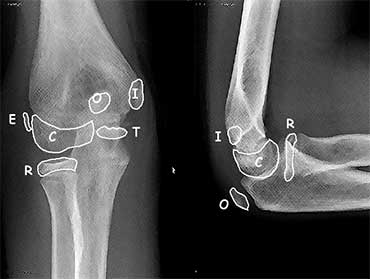

The order of appearance of the ossification centres is specified in the mnemonic C-R-I-T-O-E. The order of appearance of the ossification centres is specified in the mnemonic C-R-I-T-O-E.

Ossification centres

There are 6 ossification centres around the elbow joint.

They appear and fuse to the adjacent bones at different ages.

It is important to know the sequence of appearance since the ossification centers always appear in a strict order.

This order of appearance is specified in the mnemonic C-R-I-T-O-E (Capitellum - Radius - Internal or medial epicondyle - Trochlea - Olecranon - External or lateral epicondyle).

The ages at which these ossification centres appear are highly variable and differ between individuals.

It is not important to know these ages, but as a general guide you could remember 1-3-5-7-9-11 years.